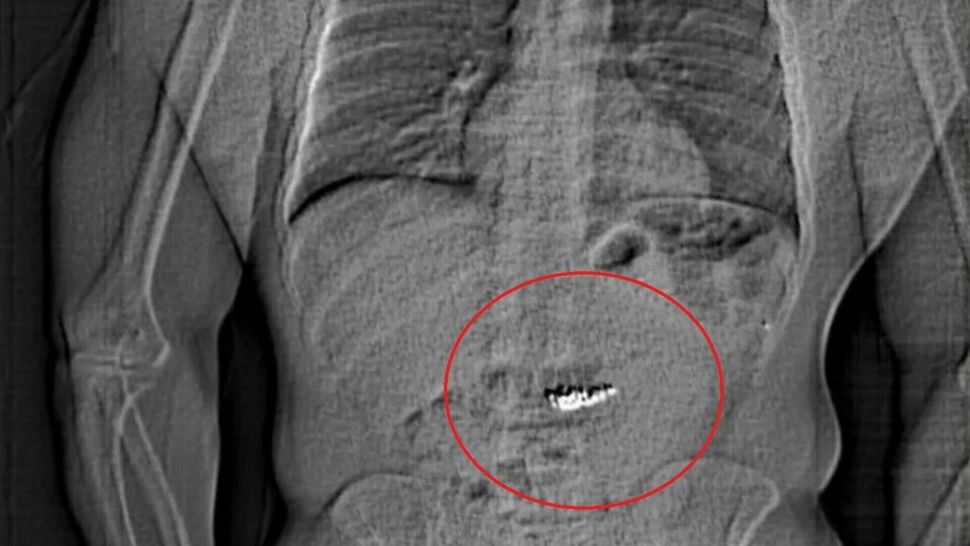

6 mar. 2025, 15:39ExternCulmea hoției: un individ a înghițit bijuterii de 700.000 de euro pentru a scăpa de poliție

9 nov. 2022, 15:17ExternBărbat prins în timp ce încerca să strecoare în avion o armă ascunsă într-un pui crud